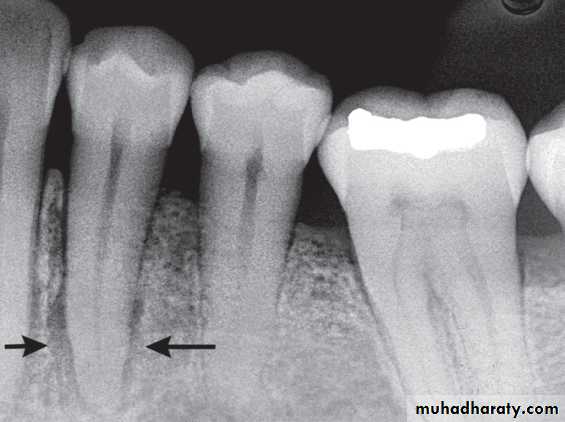

Widening of the periodontal membrane space

It is important to observe whether the widening is uniform or irregular and whether the lamina dura is still present. For instance, orthodontic movement of teeth results in widening of the periodontal membrane space, but the lamina dura remains intact. Malignant lesions can quickly grow down the ligament space, resulting in an irregular widening and destruction of the lamina duraSurrounding Bone Reaction